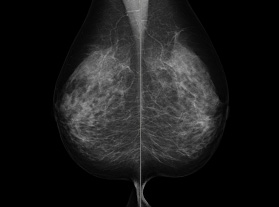

そろそろちゃんとした検診を受けなきゃです

レントゲンは片方づつ撮るの?

綺麗な形ですね

影とか無かったですか?

けんしんしといて損はなしだな

タダでしてもらってもうけたネ^^